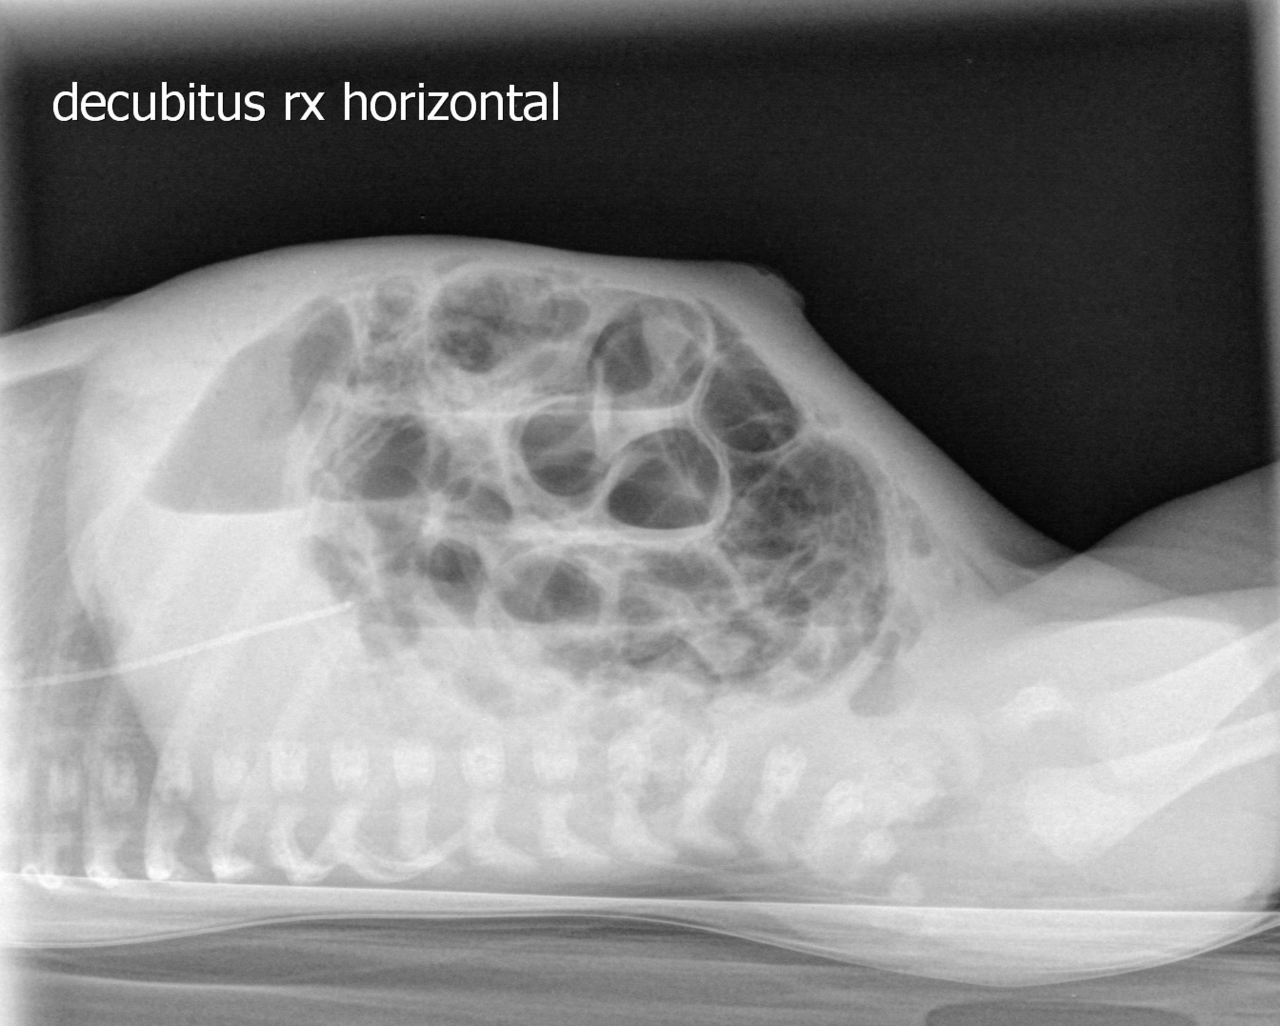

Peut compliquer la ventilation à haute pression nécessaire pour maintenir un volume courant élevé. À éliminer par une radiographie de thorax